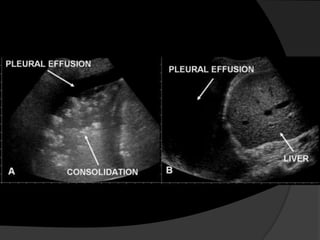

Avaliação InicialEstudos ultra-sonográficosRadiografias em decúbito lateral (Laurel)Tomografia Computadorizada (TC) para analisar o parênquima pulmonar subjacente ou mediastino.

Avaliação InicialEstudos ultra-sonográficosRadiografiasem decúbito lateral (Laurel)Tomografia Computadorizada (TC) para analisar o parênquima pulmonar subjacente ou mediastino.